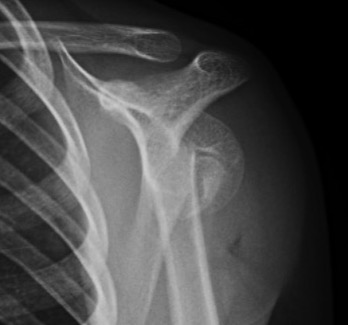

Case: 16 year old boy

Initial injury 18 months post injury